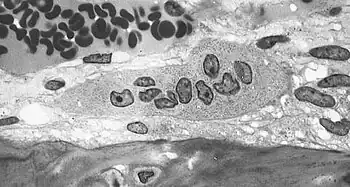

| Light micrograph of an osteoclast displaying typical distinguishing characteristics: a large cell with multiple nuclei and a "foamy" cytosol. | |

The osteoclasts are multi-nucleated cells that contain numerous mitochondria and lysosomes. These are the cells responsible for the resorption of bone. Osteoblasts are generally present on the outer layer of bone, just beneath the periosteum. Attachment of the osteoclast to the osteon begins the process. The osteoclast then induces an infolding of its cell membrane and secretes collagenase and other enzymes important in the resorption process. High levels of calcium, magnesium, phosphate and products of collagen will be released into the extracellular fluid as the osteoclasts tunnel into the mineralized bone. Osteoclasts are prominent in the tissue destruction found in psoriatic arthritis and rheumatological disorders.[3]